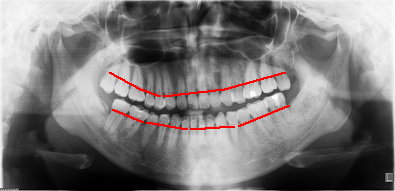

???????牙周相對(duì)健康患者牙槽骨的高度(紅線表示每個(gè)牙齒牙槽骨最高點(diǎn)的連線)

??????牙周病患者牙槽骨的高度(紅線同上,綠線則代表牙槽骨原來(lái)的水平高度)